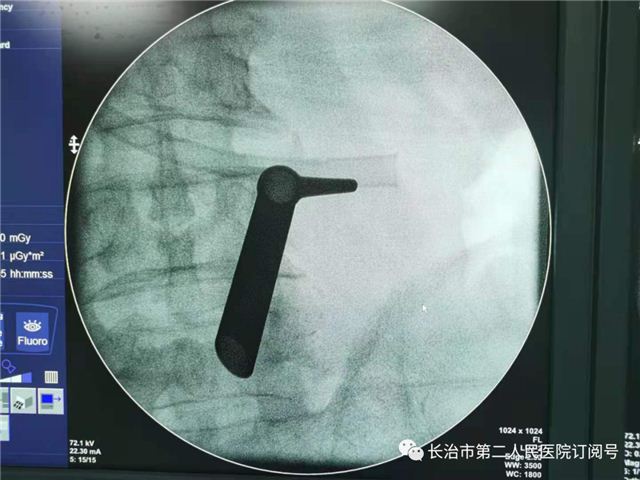

术前定位

置入通道